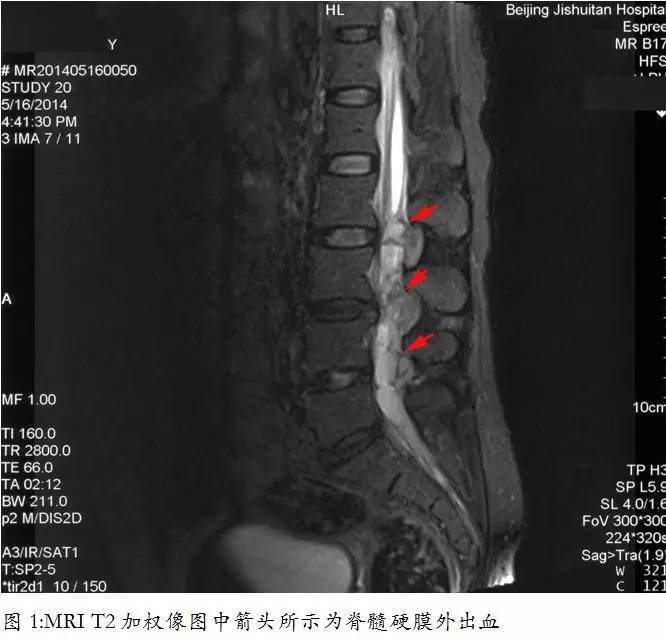

患者当日双下肢疼痛逐渐加重并出现大小便*禁失**,12小时后至专科医院就诊,急查MRI示脊髓硬膜外血肿,压迫脊髓(图1)。

MRI

T2加权像图中箭头所示为脊髓硬膜外出血(图1)。